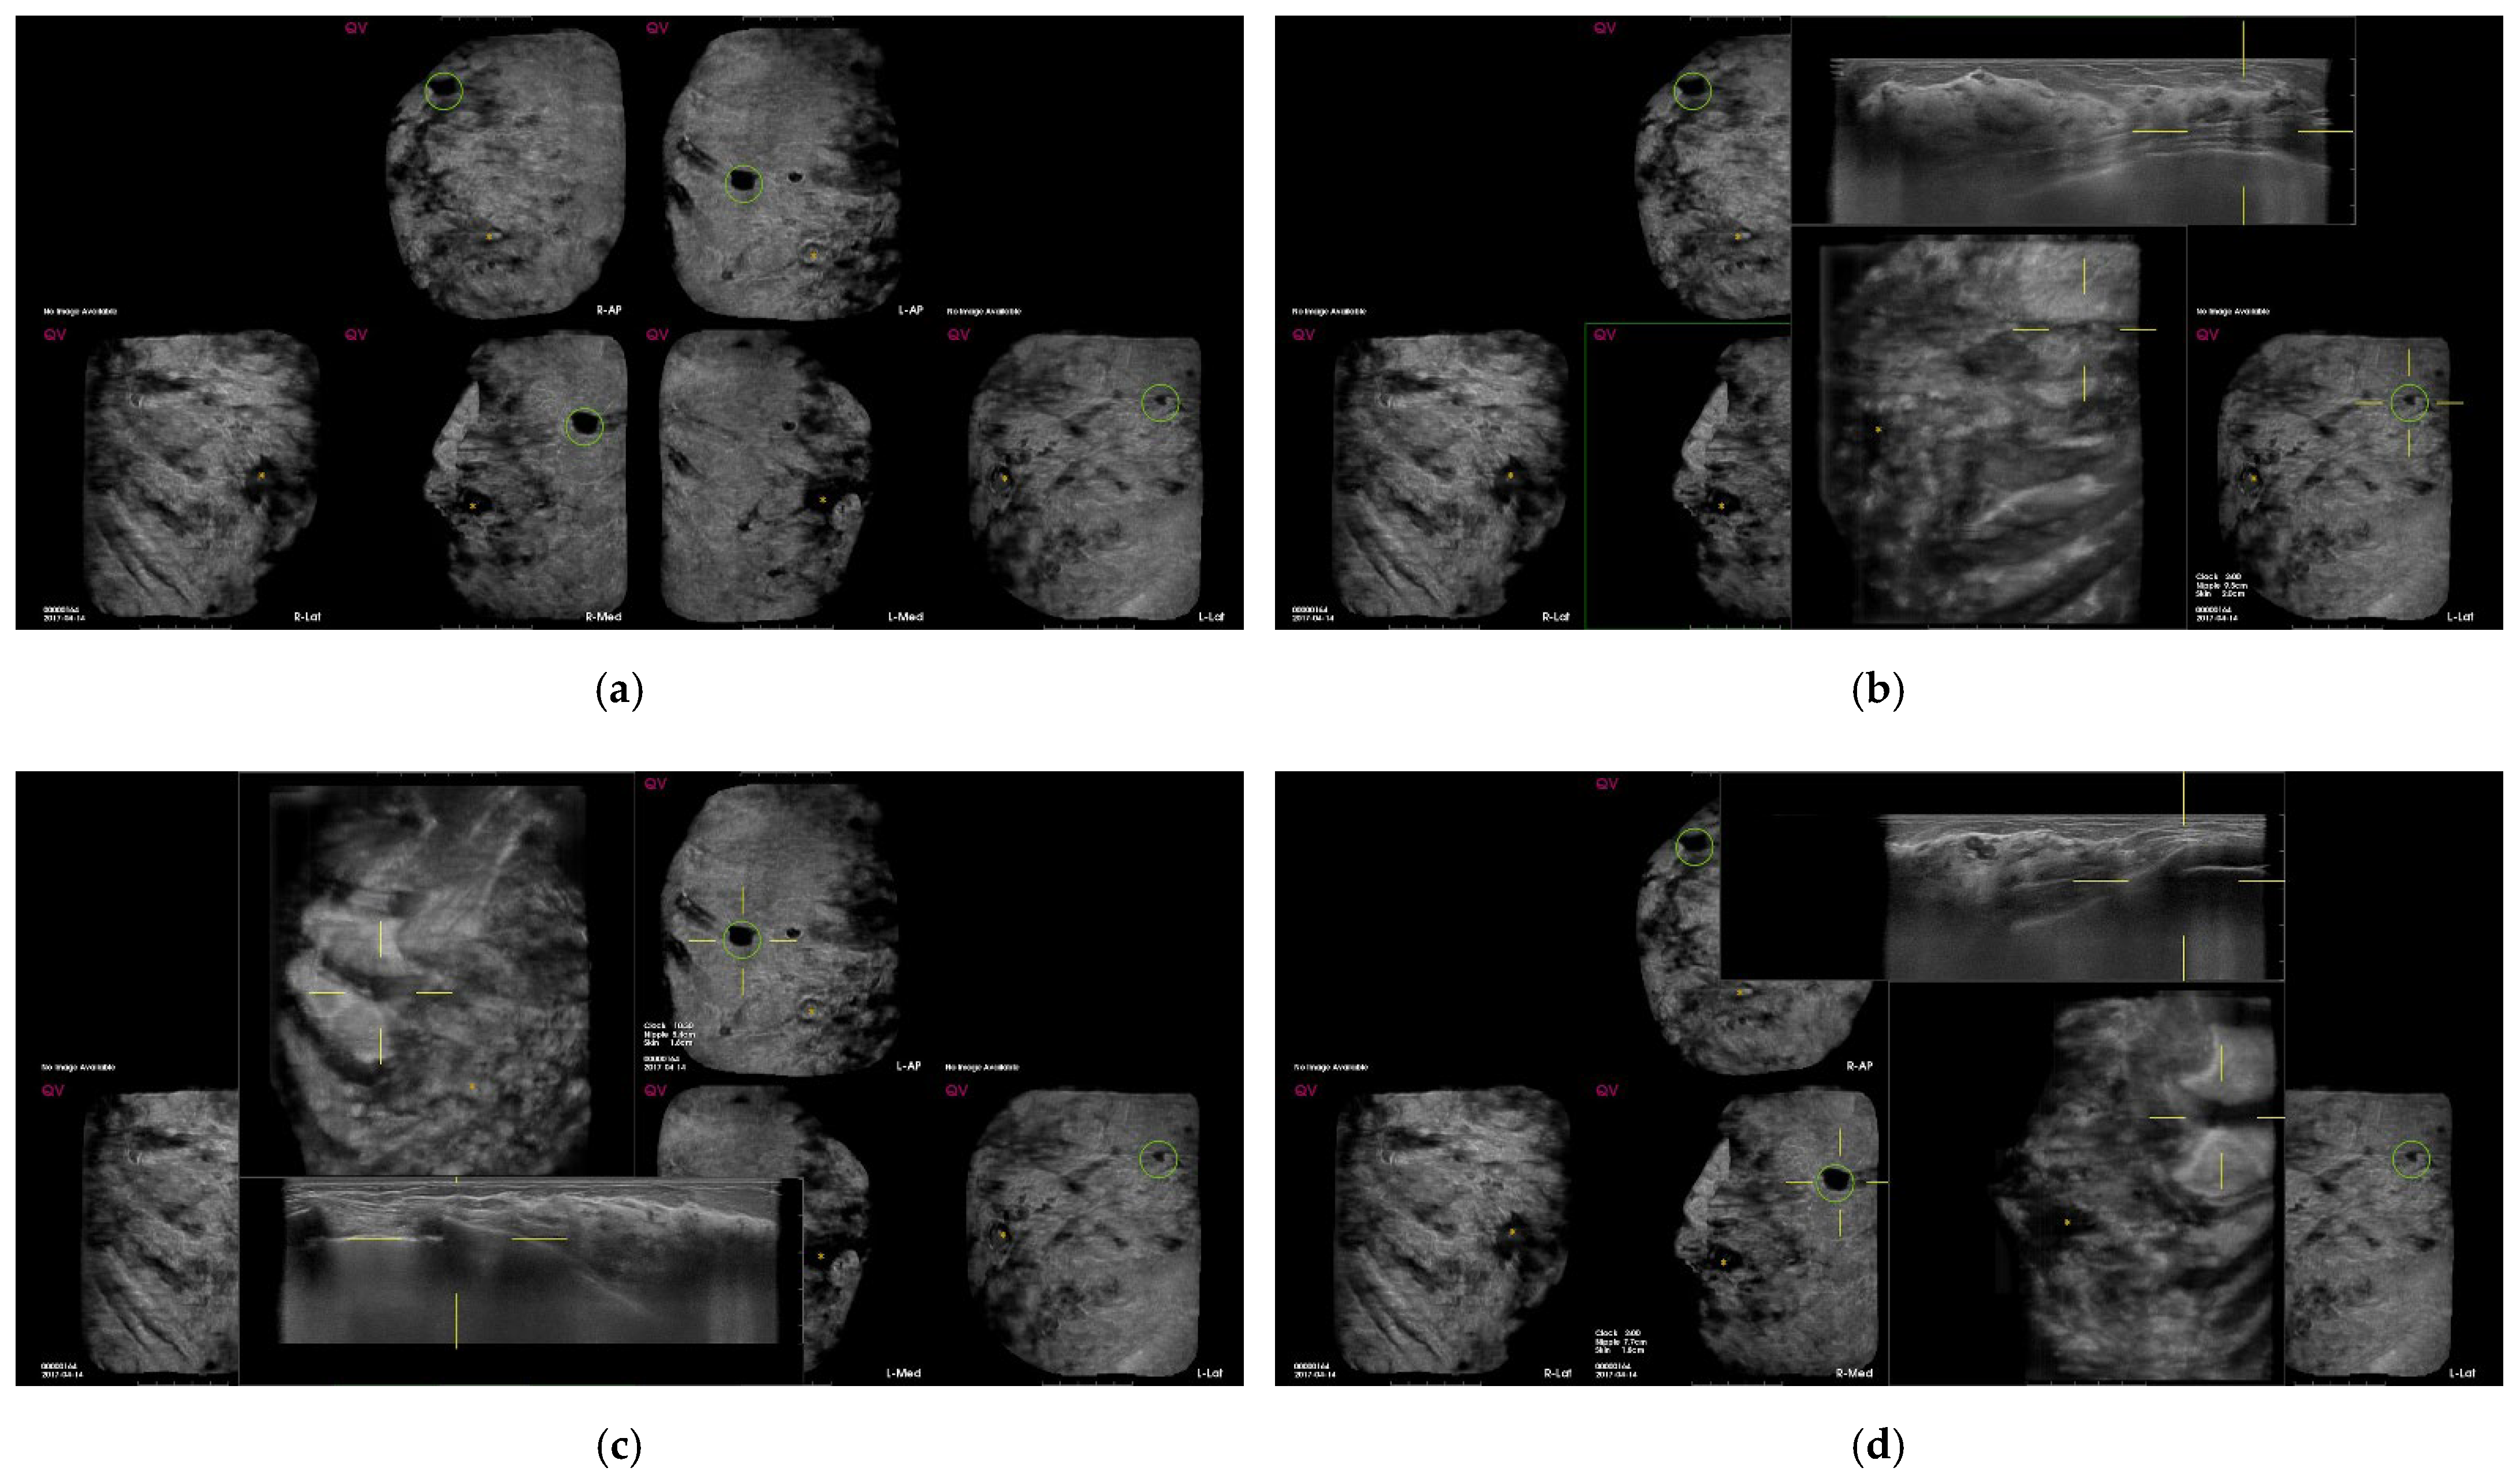

| Characteristics of CAD marks per lesion (n = 534) | n | % |

| Suspicious | 4 | 0.8 |

| Benign | 71 | 13.3 |

| Fat | 35 | 6.6 |

| Benign mass | 19 | 3.6 |

| Cyst | 9 | 1.7 |

| Fibrosis/heterogenous parenchyma | 8 | 1.5 |

| False-positive marks for pseudolesions | 459 | 86 |

| Marginal shadowing | 209 | 39.1 |

| Cooper’s ligament shadowing | 143 | 26.8 |

| Periareolar shadowing | 64 | 12 |

| Rib | 37 | 6.9 |

| Skin lesion | 6 | 1.1 |